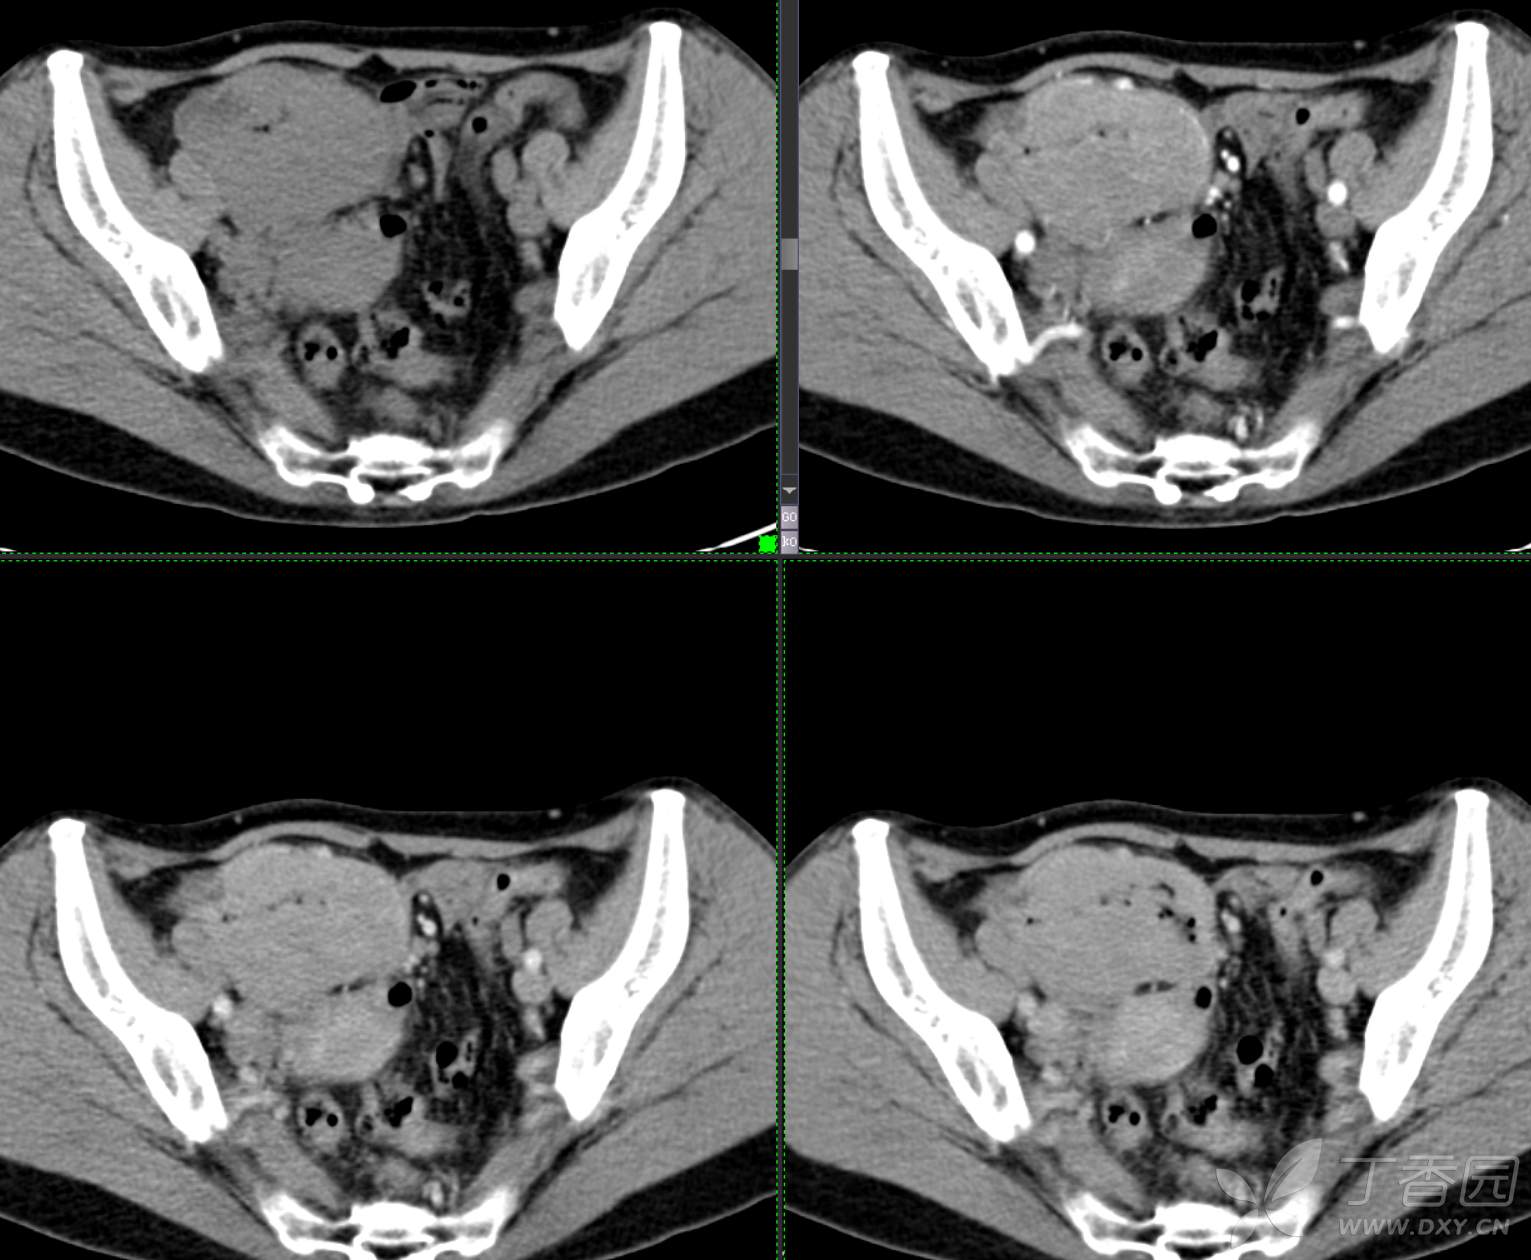

腹组13:患者,女,62岁,大便习惯改变2月余

主 诉: 【大便性状改变2月余】

现病史: 患者2月余前无明显诱因下出现大便次数增多,无明显血便黑便及粘液脓血便,大便次数由1次/日增加至2-3次/日,大便形状变细如小指,偶稀软不成形,无腹痛腹胀腹泻,无恶心呕吐、胸闷气促,肛门排气通畅,无发热盗汗。至当地医院就诊,行肠镜检查发现"回盲部占位"。为进一步治疗,我院门诊拟"回盲部肿瘤"收住入院。